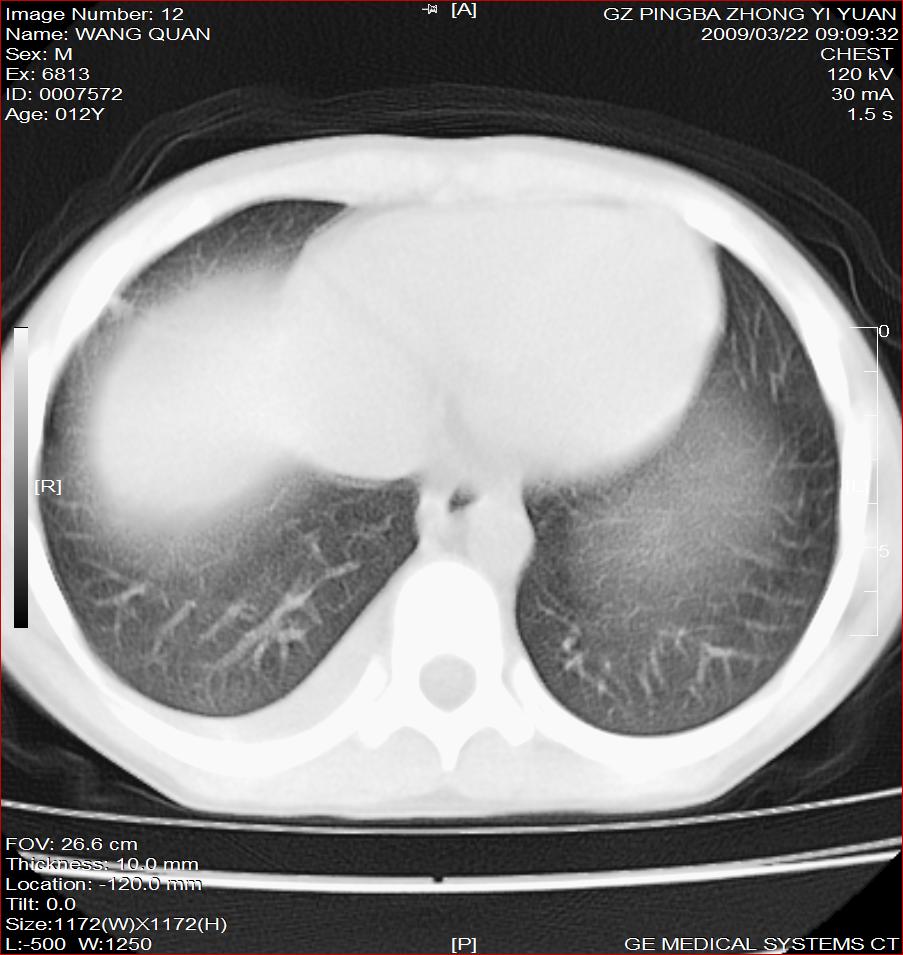

以下是引用dyqct在2009-3-22 21:12:00的发言:[br]右侧支气管内膜结核继发肺内感染,右侧胸膜腔少量积液。支持!

以下是引用随光逐影在2009-3-23 8:12:00的发言:[br]1)右肺门及纵隔淋巴结结核。2)两肺急性血行播散型肺结核可能。3)右侧支气管内膜结核?建议必要时行纤支镜检查。4)右侧少量胸腔积液。